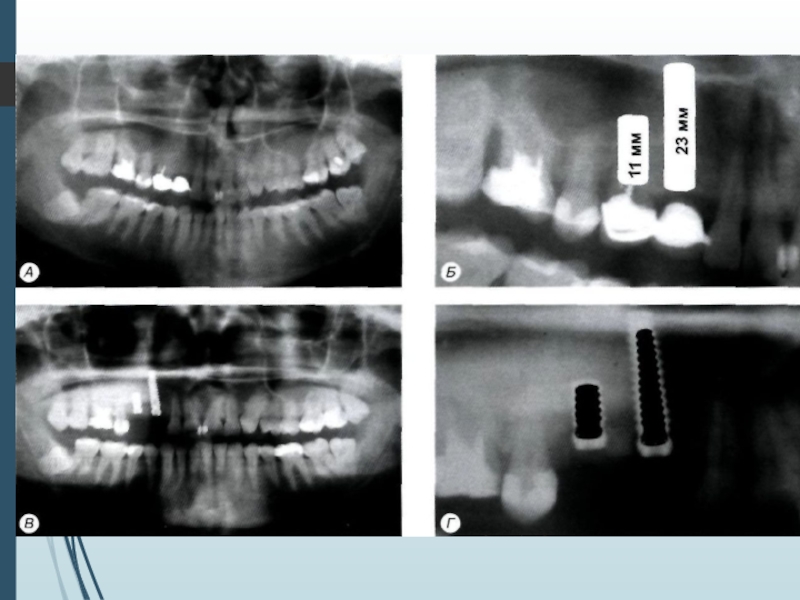

Слайд 11Однако следует учитывать, что даже при пра-

вильной укладке и

методике ортопантомография

даёт искажения реальных размеров челюстей до

10% по

вертикали и до 20% по горизонтали.

При неправильном положении пациента во вре-

мя обследования или нарушении режима рабо-

ты ортопантомографа искажения (увеличение

размеров) могут достигать 32% по вертикали и

50-70% по горизонтали

Однако следует учитывать, что даже при пра- вильной укладке и методике ортопантомография даёт искажения реальных размеров челюстей